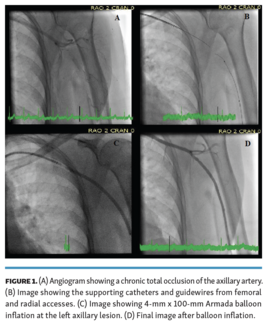

Ibrahim Halil Inanc, MD; Vasili Lendel, MD; Konstantinos Marmagkiolis, MD, FACC, FSCAI; Cezar A. Iliescu, MD, FACC, FSCAI; Ismail Ates, MD; Thomas E. Milner, PhD; Nitesh Katta, PhD, MSc; Marc D. Feldman, MD; Mehmet Cilingiroglu, MD, FSCAI, FACC, FESC, FAHA

The Pantheris device (Avinger), an integrated version of IV-OCT in a directional atherectomy device, has been used for the revascularization of lower extremity occlusions. We present a 73-year-old patient with chronic total occlusion of the...